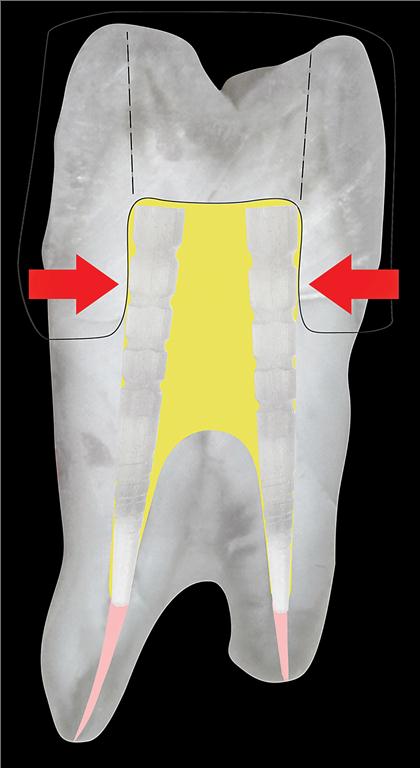

Should a tooth be saved or should it be extracted and an implant placed? Is basing a comparison between implant retention and RCT success on endodontic outcome measures reliable? The short answer is no. Strindberg’s criteria (1956) and the PAI index (Ørstavik et al., 1996) are widely accepted as measures of RCT success. Generally, RCT … Read more